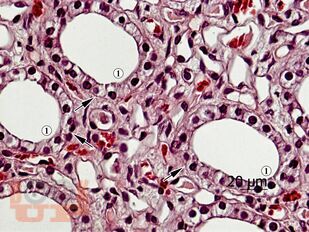

Учебное пособие выполнено в формате, удобном для изучения гистологии русско- и англоязычными студентами медицинских вузов. Все тексты даны на двух языках в сжатом объёме, но без потери сведений, имеющих принципиальное значение. В пособии представлены все основные разделы изучаемого предмета – гистологическая техника, цитология, общая и частная гистология, эмбриология человека. Издание иллюстрировано оригинальными микрофотографиями, сделанными авторами с микропрепаратов, изготовленных в ЗАО "Ретиноиды". Подрисуночные подписи и обозначения выполнены также на двух языках.